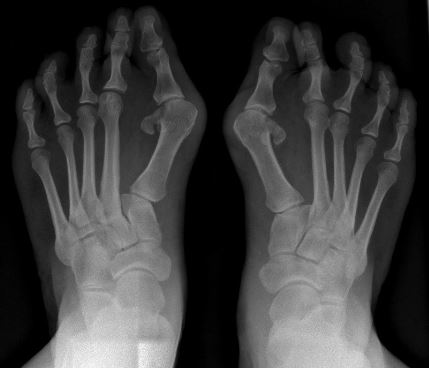

- Вальгусная деформация большого пальца стопы с микродактилией и монопалангией большого пальца являются ранними признаками, которые часто видны при рождении.[1]

Вальгусная деформация большого пальца стопы - Кифосколиоз и лордоз[4]

Фибродисплазия оссифицирующая прогрессирующая может быть легко неправильно диагностирована, но это можно избежать, проверив пальцы пациента на наличие вальгусной деформации большого пальца и укороченного большого пальца, а также проведя тщательное клиническое обследование и тест на положительный результат гена ACVR1.[5] Генетическое тестирование теперь можно проводить для подтверждения диагноза ФОП до появления гетеротопической оссификации, что может избежать возможных инвазивных методов лечения и диагностических тестов.[3]